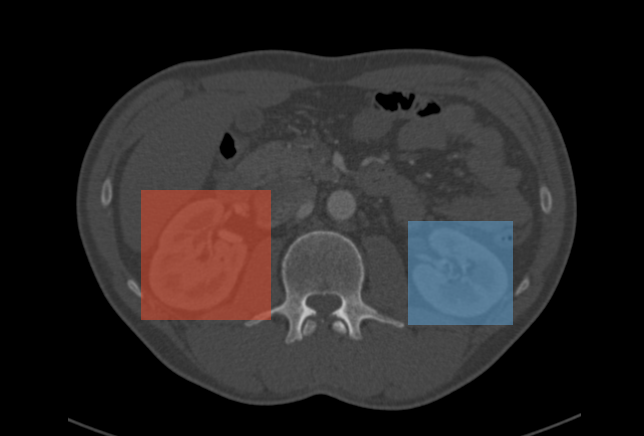

The results of applying a YOLOv3 object detection model are a series of 2D boxes around the objects of interest, as shown in the following examples.

Kidneys